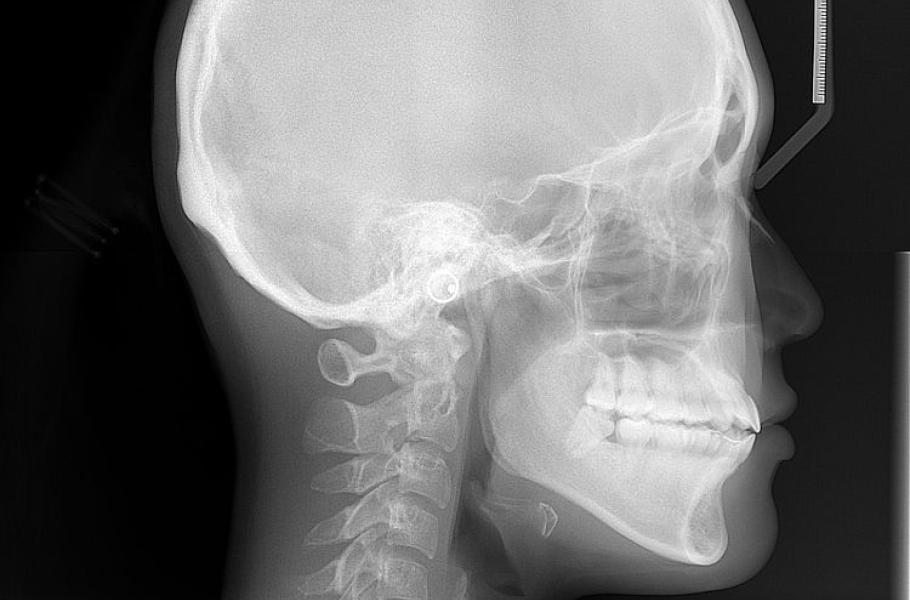

Na Univerzitě v Rochesteru řeší vývojové poškození lebky, známé jako kraniosynostóza. Jde o to, že se předčasně uzavře jeden nebo více švů lebky nenarozeného dítěte, což způsobí její deformaci. Postižené děti se vyvíjejí pomaleji a předčasně zpevněná lebka jim stlačuje mozek, což může vést i ke smrti dítěte. Řešením by mohly být kmenové buňky.

Kosti lebky se vyvíjejí jinak, než kosti ve zbytku těla. Mají to na starost jiné kmenové buňky. A až teď se rochesterskému týmu povedlo objevit ty správné kmenové buňky, které jsou zodpovědné za růst lebečních kostí. Za nějaký čas a po nezbytném výzkumu bychom těmito kmenovými buňkami mohli spravovat poškozené lebky.